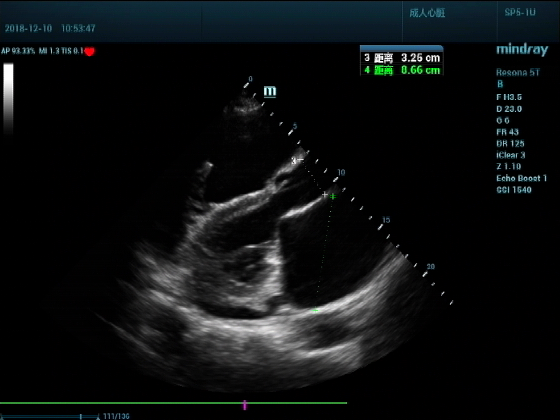

超声可见:左房,右房,右室明显增大,主肺动脉及右肺动脉增宽,二尖瓣中度反流,三尖瓣重度反流,肺动脉轻度高压,心律不齐

心包积液盆腔积液。淤血性肝增大,肝静脉增宽。(右心衰声像改变)